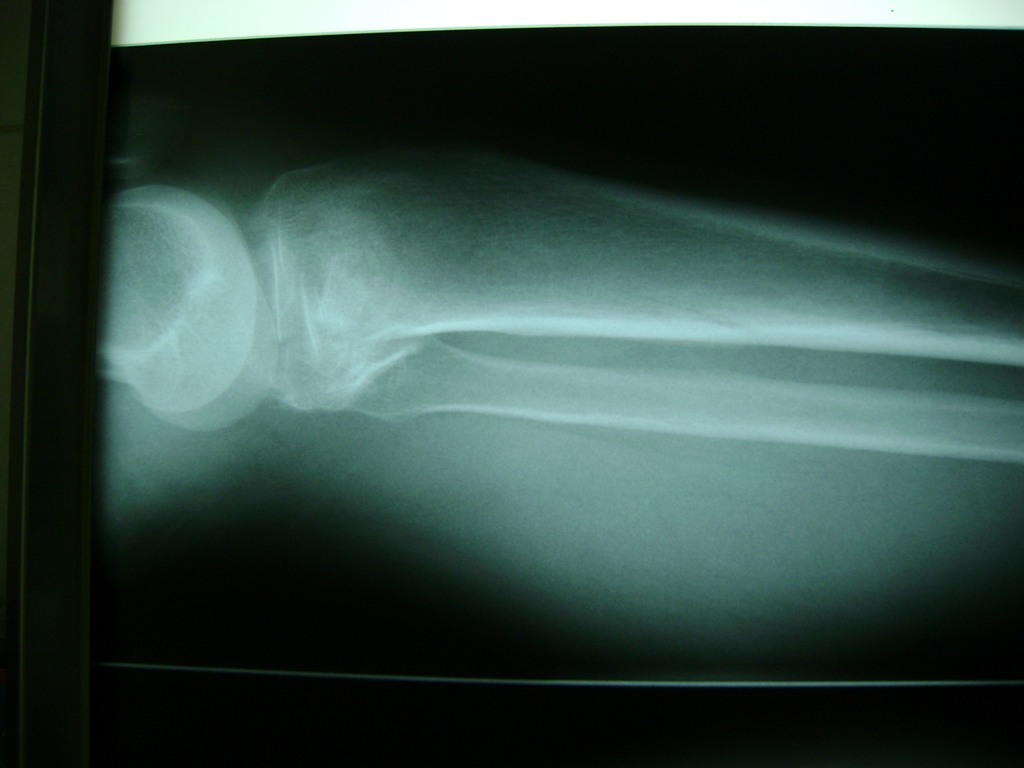

Cirugías de Muñecas